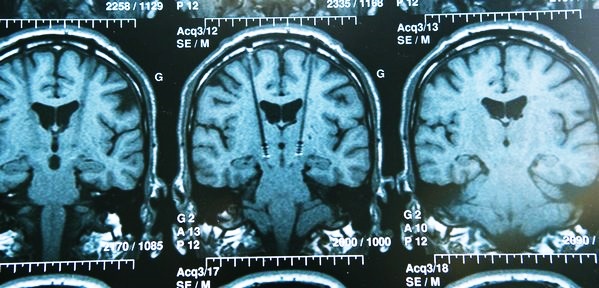

При наличии частого головокружения, обморочного состояния требуется консультация невропатолога, проведение реоэнцефалографии и УЗИ сосудов шеи, головы. РЭГ помогает выявить патологические изменения в сосудах, например, затруднение венозного оттока. При необходимости проводят МРТ головного мозга.